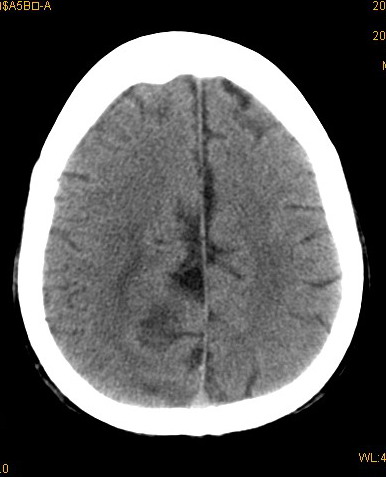

以下是引用卜一在2008-8-14 16:31:00的发言:[br]支持:巨脑回伴脑积水!另:胼胝体发育不良!

以下是引用随光逐影在2008-8-14 16:58:00的发言:[br]胼胝体发育不良;脑积水。

以下是引用同在2008-8-14 19:46:00的发言:[br]巨脑回伴积水,胼胝体发育不良.